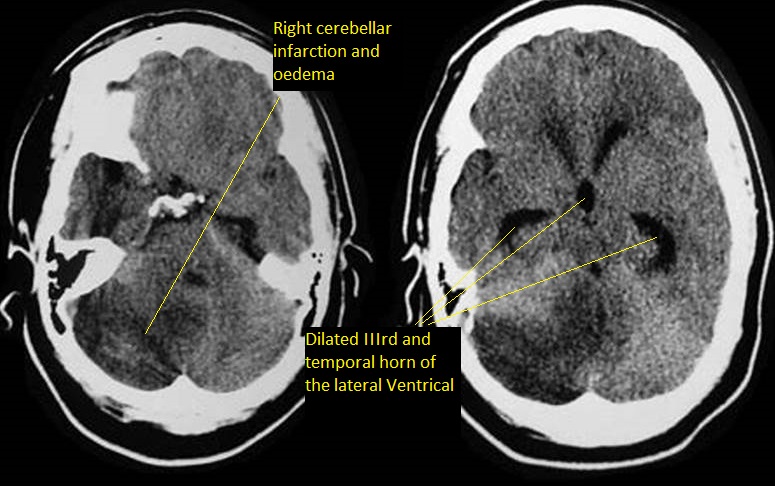

• Cerebellar Ischaemic Stroke

• Cerebral Amyloid angiopathy (CAA) ✅